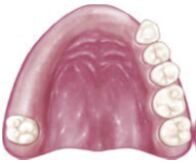

26.下圖可撤式局部義齒設計的間接固位體(indirect retainer)位置之考量,下列何處最為合適? (A)左上第二小臼齒 (B)左上第二大臼齒 (C)右上第二大臼齒 (D)左上犬齒